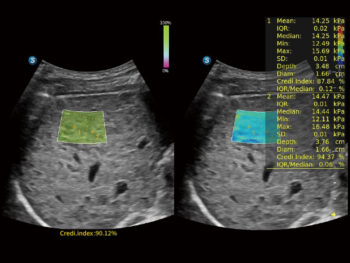

Shear Wave Elastography (SWE)

Технологи нь элэгний фиброзыг тоон байдлаар үнэлэх боломжийг олгож, оношлогооны нарийвчлалыг нэмэгдүүлдэг. Нэмэлтээр, чанарын газрын зураг (quality map) харуулснаар эмчийн итгэлтэй онош тавих боломжийг сайжруулдаг.